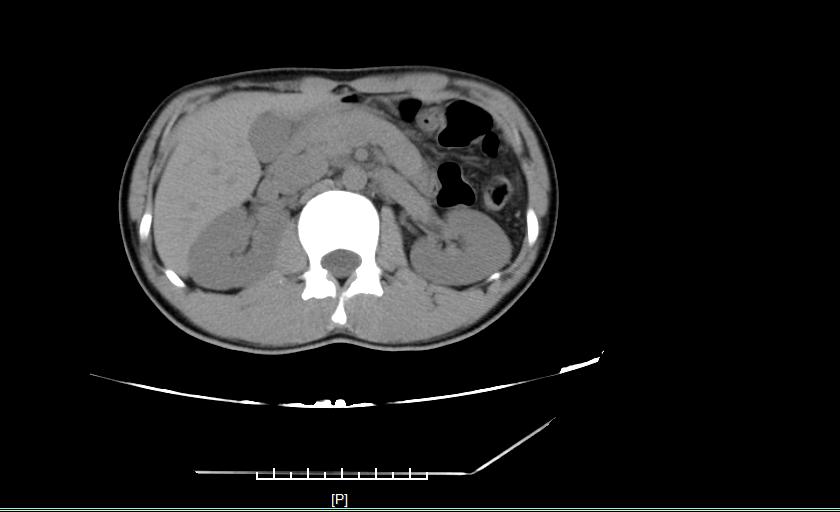

入院后查体:腹平坦,腹式呼吸减弱,无腹壁静脉曲张,未见肠型及蠕动波,腹壁柔软,中上腹及左下腹压痛阳性,无反跳痛,无肌紧张,腹部未触及包块,肝脾肋下未可触及,Murphy征阴性,移动性浊音阴性,肠鸣音较弱,未闻及血管杂音;肛门指检,未触及异常肿物,退指指套可见暗红色血迹。腹部CT提示:急性胰腺炎,消化道出血?予以胃肠减压、抑酸、抑酶、抗感染等治疗2天,腹痛缓解不明显,需间断止痛治疗,四肢远端逐渐出现红色、对称的斑丘疹,并快速向近心端蔓延。考虑诊断为:腹型过敏性紫癜,加用激素,次日腹痛明显缓解,四肢皮疹颜色逐渐变暗,治疗五天后,腹痛完全缓解,四肢皮疹基本消失,激素逐渐减量并停药。